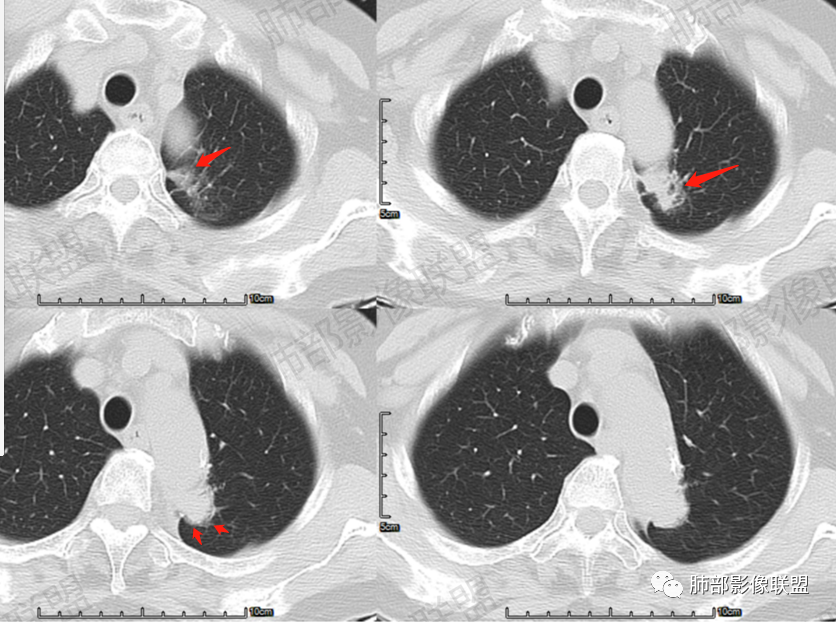

尘缘:病灶沿主动脉匍匐样生长,但整体明显膨隆,胸膜牵拉凹陷,局部有小喇叭口样改变。

尘缘:边界清楚的GGO。

尘缘:局部血管增粗,扭曲

尘缘:局部有淋巴管增粗,小叶间隔增厚,提示癌淋可能。

尘缘:最后就是强化,虽然是明显渐进性强化,要考虑炎性可能,但腺癌明显渐进性强化的并不少见。